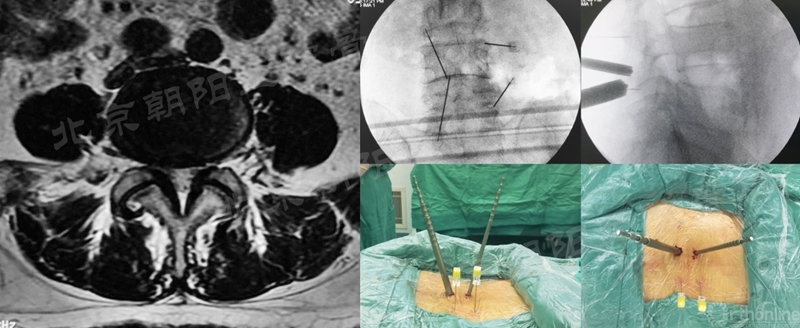

#12例UBE,PLIF术后8年L3/4 ASD。

#9例UBE,ADS合并L4/5LDH。

术前MRI和术中定位